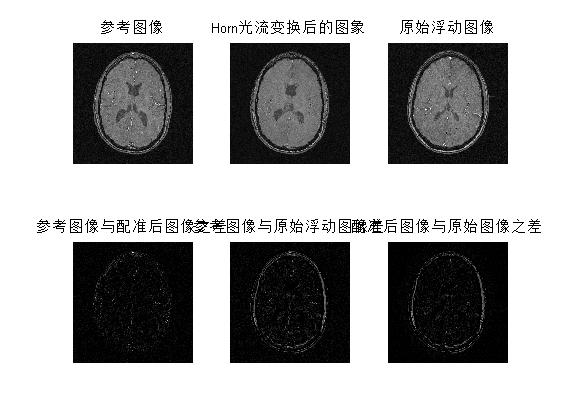

三、运行结果